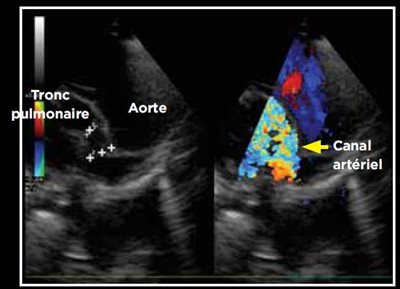

Photo 3 - Persistance du canal artériel, mode bidimensionnel sur une coupe longitudinale des gros vaisseaux par abord parasternal crânial et dorsal gauche.

Photo 5 - Mesure des trois principales dimesions du canal artériel : largeur à la naissance et à l’abouchement, longueur.

Le canal artériel est visualisé dans 96 % des cas en mode bidimensionnel ou en mode Doppler couleur sur une coupe petit axe transaortique par abord parasternal droit (Photo 1), sur une coupe petit axe par abord parasternal crânial gauche (Photo 2), ou plus facilement sur une coupe longitudinale des gros vaisseaux (aorte et tronc pulmonaire) par abord parasternal crânial et dorsal gauche (Photo 3).

La mesure de la taille du canal est réalisée en mode bidimensionnel ou en mode Doppler couleur, après identification. Les deux modes de mesures sont valables, la mesure en mode bidimensionnel étant la plus précise.

La mesure concerne la longueur du canal, la largeur à sa naissance sur l’aorte, et la largeur à son abouchement au niveau du tronc pulmonaire (Photo 5) [2].